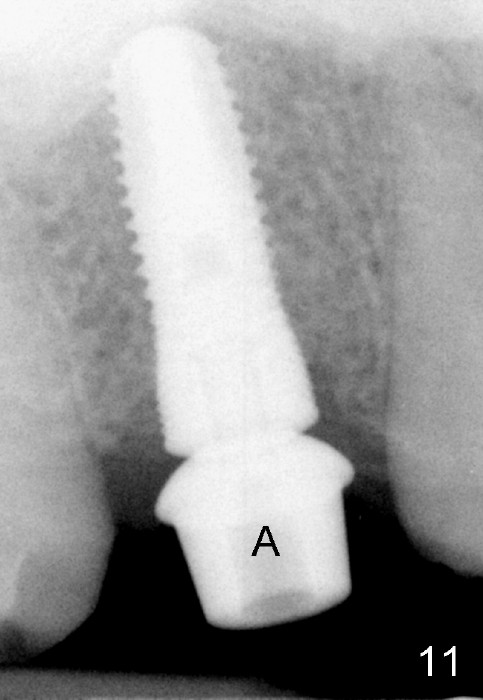

The bone density (Fig.1 white *) at the edentulous area (#3) is lower than that at the dentulous one (black *, 50 year-old man). The buccal plate is also atrophic and concave (Fig.2,3 arrowheads). A series of bone expanders are used to form osteotomy (following 1.6 mm pilot drill) at the depth of 14 mm (Fig.3 E 3.0 mm in diameter). When the last expander (4.3 mm) is removed from the osteotomy, the buccal plate appears to have been moved buccally (Fig.5 arrowheads). A 5.3x14 mm submerged implant (Fig.6 I) is placed with insertion torque >35 Ncm. The buccal plate seems to improve following placement of an 8.2 mm healing abutment and suturing (Fig.7). No bone graft is used. The buccal plate remains normal 12 days postop (Fig.8). It is slightly concave 3 months postop (Fig.9) with minimal bone resorption at the crest (Fig.10 (H: healing abutment),11 (A: cemented abutment). Nine months post cementation (12 months postop), bone resorption at the crest remains minimal (Fig.12) while the buccal plate (Fig.13 *) at #3 remains strong. Bone loss appears not to get worse 22 months post cementation (Fig.14). Soft and hard tissues remain healthy around the implant crown 3 years (Fig.15) and 3.5 years (Fig.16,17) post cementation.